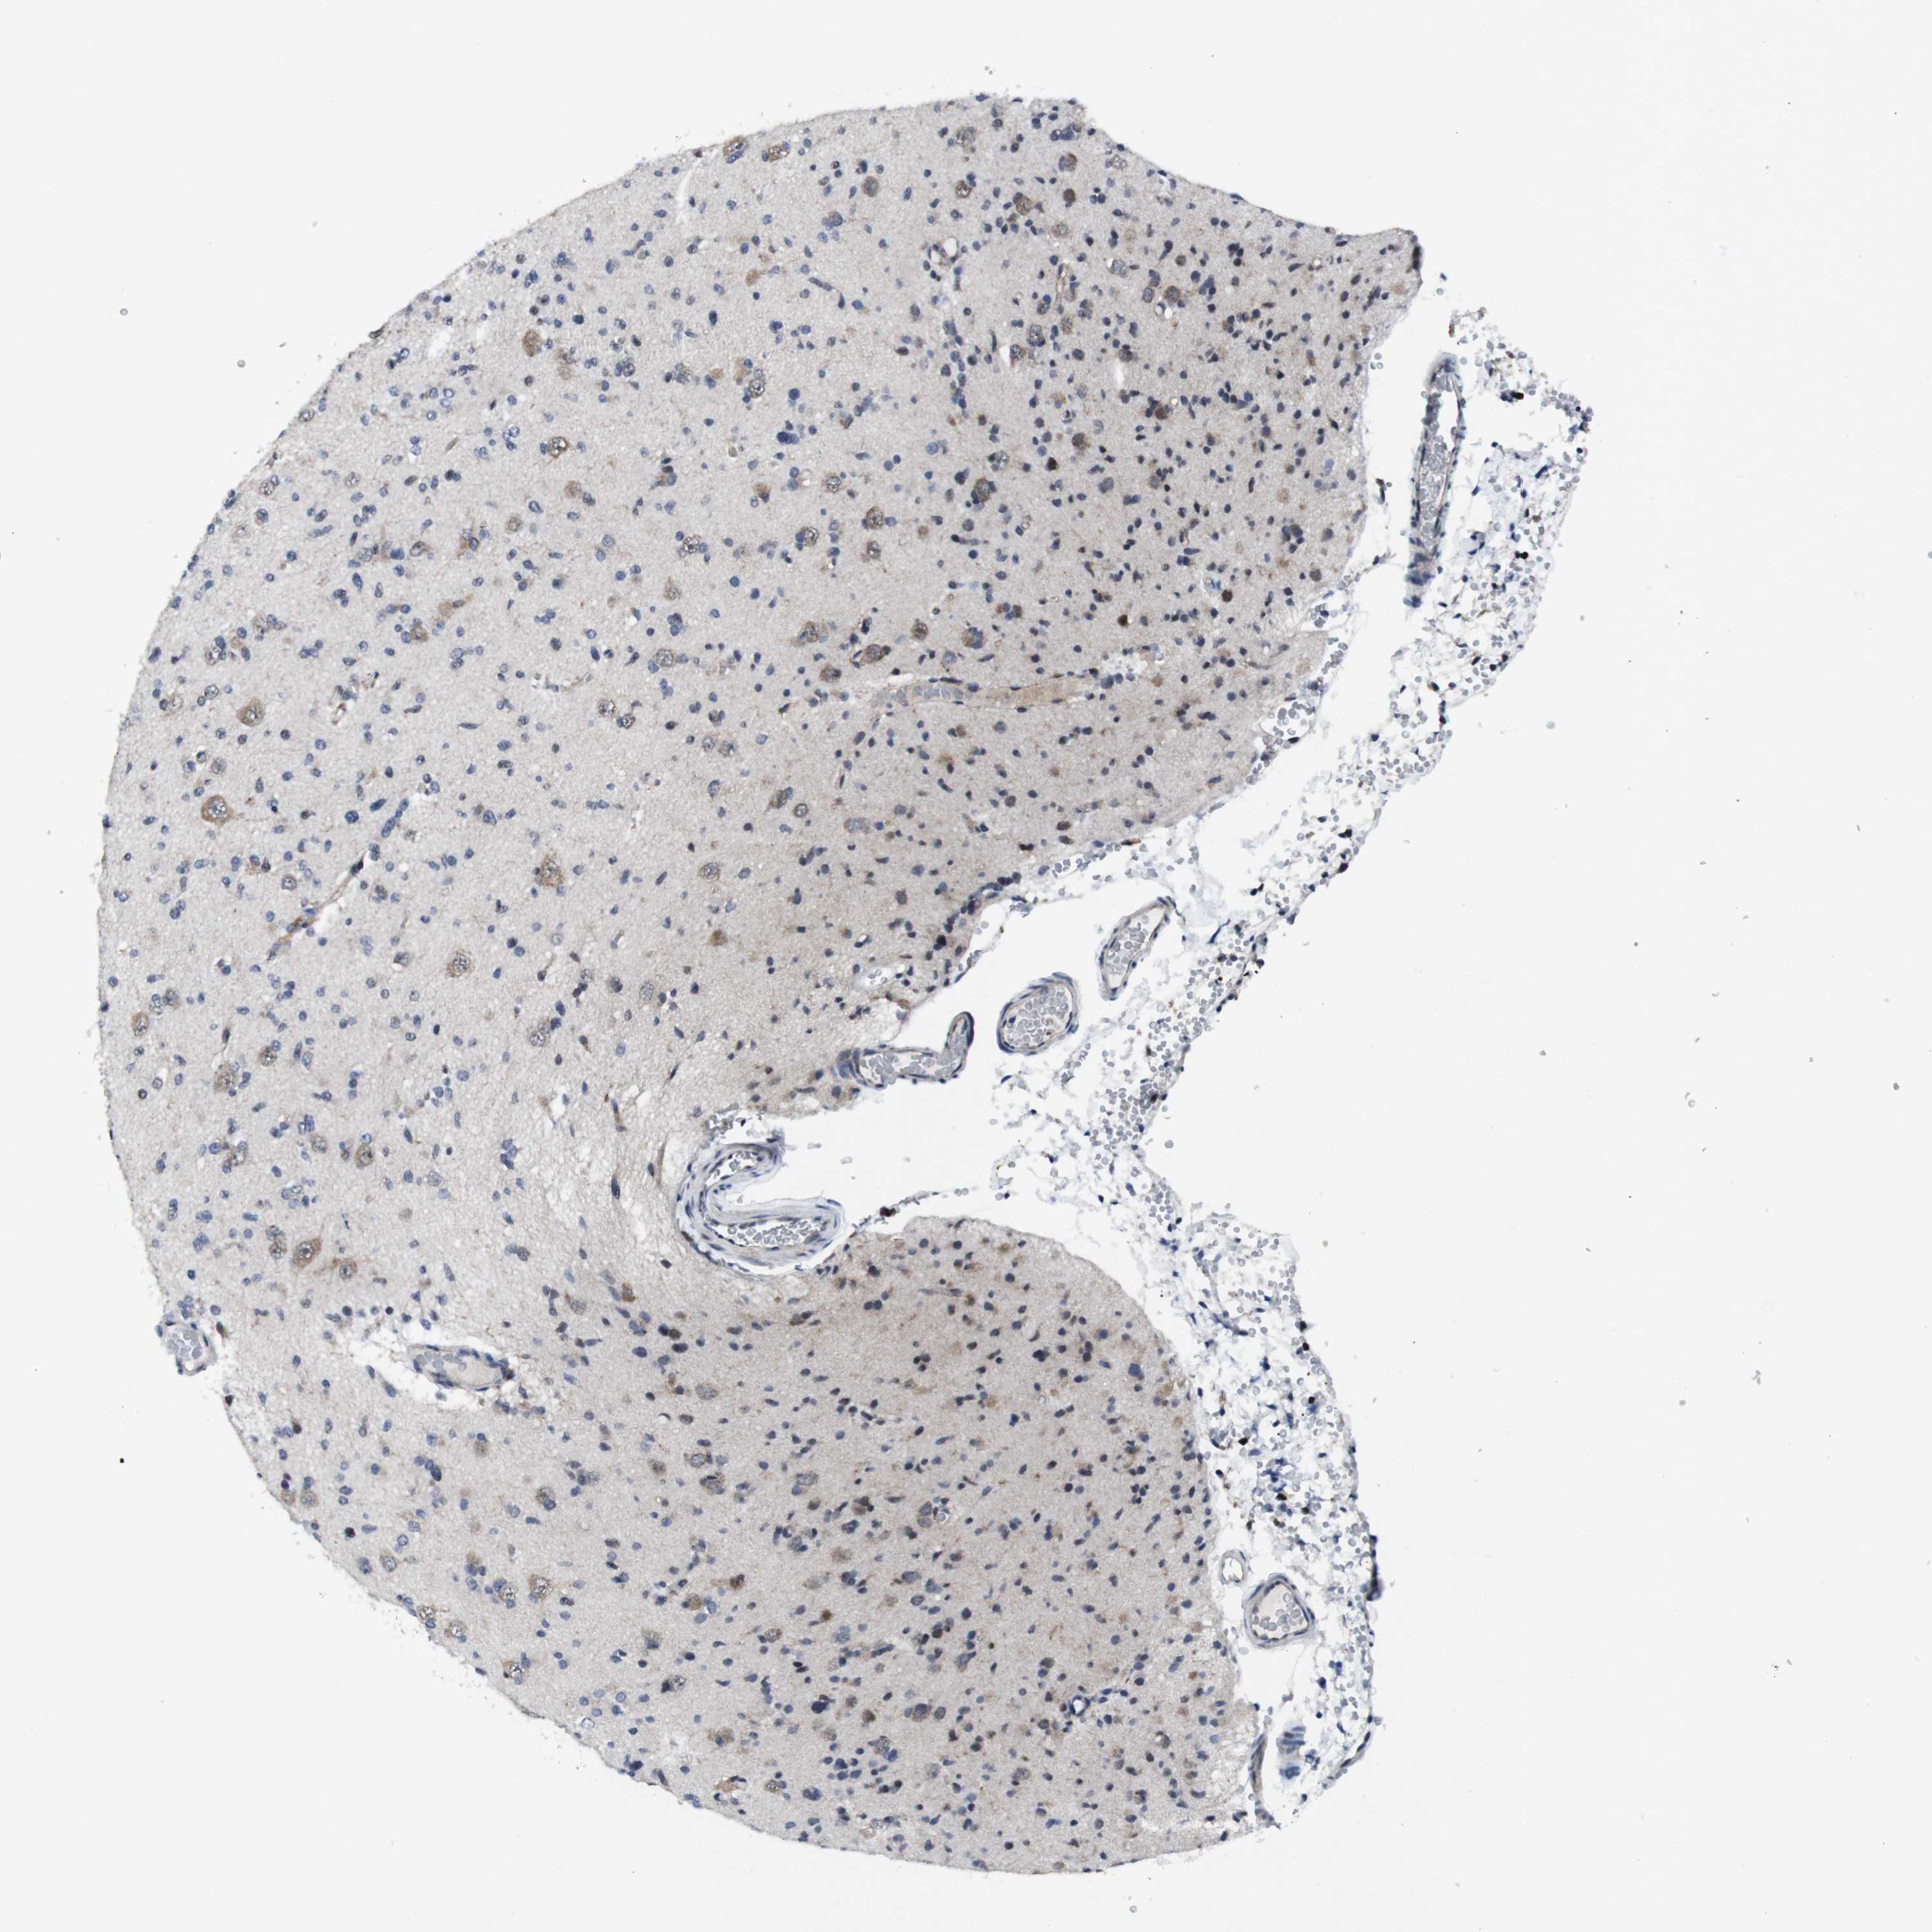

GLIOMA - Protein expressioni

A mouse-over function shows sample information and annotation data. Click on an image to view it in a full screen mode. Samples can be filtered based on level of antibody staining by selecting one or several of the following categories: high, medium, low and not detected. The assay and annotation is described here.

Note that samples used for immunohistochemistry by the Human Protein Atlas do not correspond to samples in the TCGA dataset.

Antibody stainingi

Antibody staining in the annotated cell types in the current human tissue is reported as not detected, low, medium, or high, based on conventional immunohistochemistry profiling in selected tissues. This score is based on the combination of the staining intensity and fraction of stained cells.

Each image is clickable and will lead to virtual microscopy that enables deeper exploration of all samples and also displays staining intensity scores, fraction scores and subcellular localization as well as patient and tissue information for each sample.

Antibody HPA001860

Antibody CAB013108

Staining

High

Medium

Low

Not detected

Intensity

Strong

Moderate

Weak

Negative

Quantity

>75%

75%-25%

<25%

None

Location

Nuclear

Cytoplasmic/membranous

Cytoplasmic/membranous,nuclear

Glioma, malignant, High grade

Glioma, malignant, Low grade